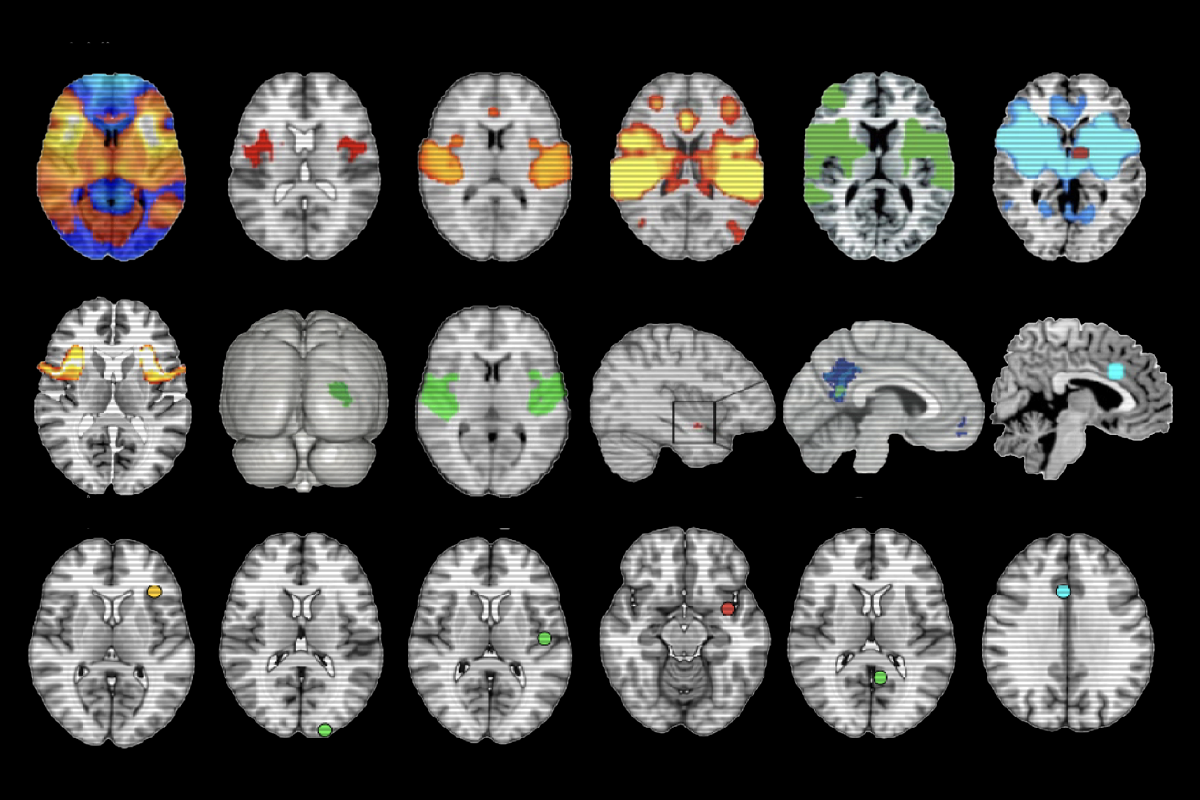

n LNM, researchers identify the locations of brain lesions in people with a given neurological condition, such as schizophrenia, and then overlay those sites on top of a reference connectome from healthy people. The networks intersected by those sites are likely to be affected by the lesions, and thus could contribute to the condition, the thinking goes.